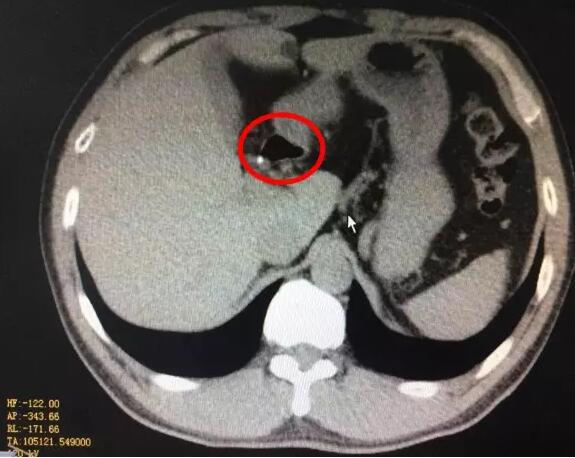

很快,化验结果出来了,血淀粉酶2714U/L,腹部CT提示胰腺水肿,急性胰腺炎诊断明确。立即给予胃肠减压、制酸、抑酶等综合治疗。第三天复查CT提示坏死性胰腺炎,只有少量胰腺组织残留,并出现肺功能、肝功能受损和腹腔积液等并发症。